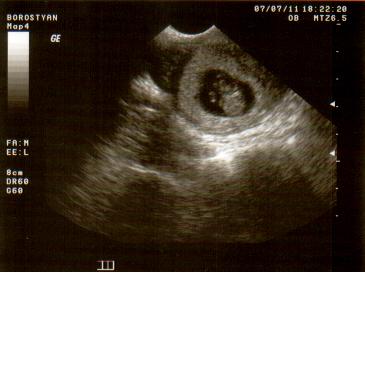

Szóval a szerda története, amikor kiderült, hogy két babánk lesz egyszerre:

Tegnapelőtt kellett visszamennem a dokihoz, aki hétfőn szabadságra megy 3 hétre. Rávettem a páromat, hogy kisérjen el, és örülök, hogy eljött velem, mert egyedül nem biztos, hogy hazataláltam volna! Szerdán tehát visszamentem kontrollra, ahol nagyon jól elbeszélgettünk az orvossal, megkérdezte, hogy hogyan érzem magam, van-e panaszom. (Szegény párom szerintem már itt rágta a körmét a váróban, mert a többiek előttem max. 5 percig voltak bent!) Mikor befejeztük a helyzetelemzést elkezdte a vizsgálatot. Közölte, hogy a méhszáj zárt, nagyon jó! Következett az UH-os vizsgálat. Már az elején sejtettem, hogy valami van, mert néha elég érdekes lett a feje! Hosszas vizsgálódás után megkérdezte az orvos, hogy mit szólnék ha azt mondaná, hogy ketten vannak?! Teljesen lefagytam! Mondtam neki, hogy két gyereket szerettünk volna, de nem egyszerre! Azóta sem tudom felfogni a dolgot, egyenlőre ott tartunk, hogy a párommal győzködjük egymást a UH felvételt nézegetve, hogy megtörtént velünk is a csoda, ikreink lesznek! (Remélem, minden rendben lesz velük, nem fog kiderülni semmi negatív dolog, mert kezdem magam teljesen beleélni a dupla baba gondolatába! :oops: :roll: )

Kép 9 hetesen az egyik Kép 9 hetesen a másik

rnecsi

Sajnálom lányok! Az egyik nagyon szégyelős! Lehet, hogy kislány? :lol:

Sikerült előcsalogatni! :D